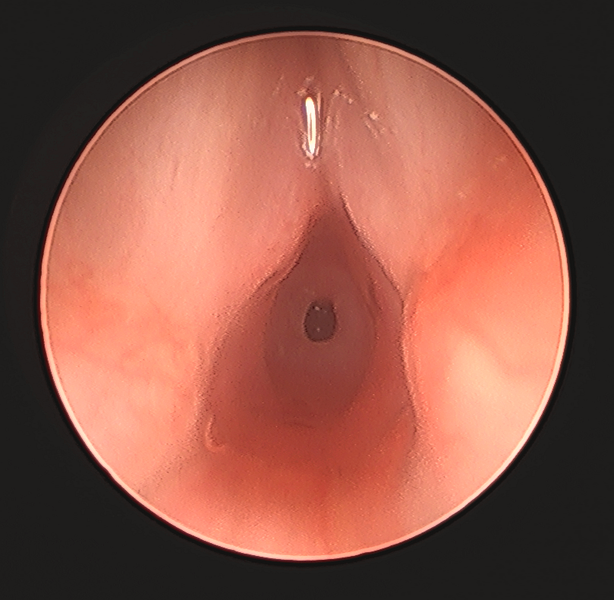

Subglottic Stenosis